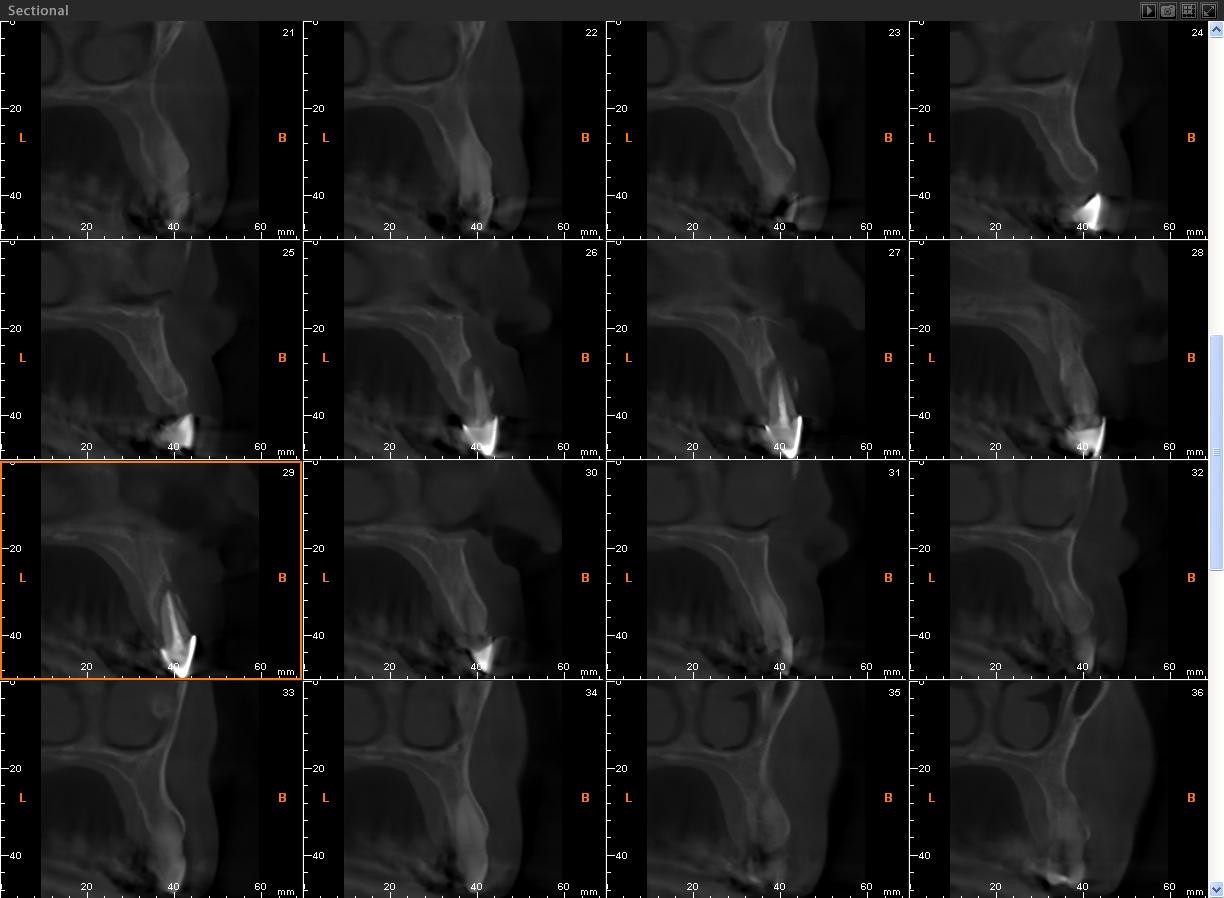

Maxilar